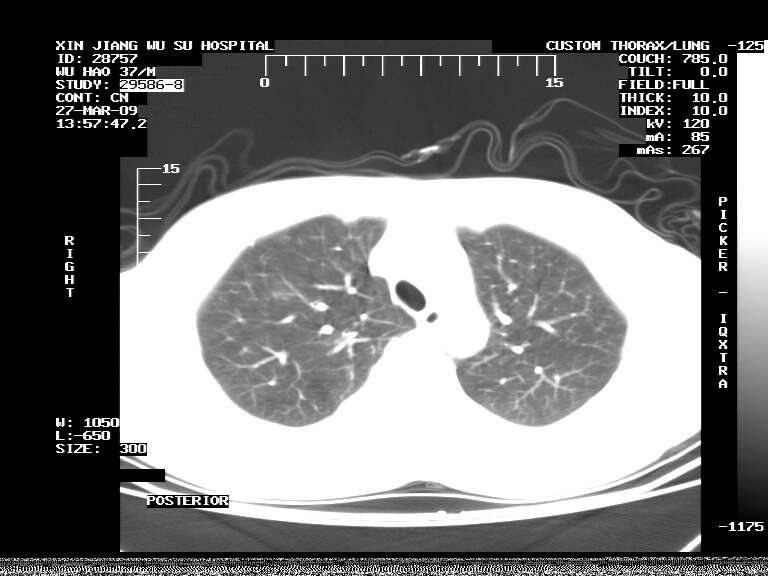

男,37岁,体检胸透发现阴影。

患者体检发现 无症状 左肺下叶占位,边缘模糊,可见血管聚束、分叶、胸膜牵拉,增强呈不均匀性强化。 首先考虑左肺下叶周围型肺癌,建议穿刺活检。

患者体检发现 无症状 左肺下叶占位,边缘模糊,可见血管聚束、分叶、胸膜牵拉,增强呈不均匀性强化。 首先考虑左肺下叶周围型肺癌,建议穿刺活检。支持!

左肺下叶见一结节病变,边缘欠清不光滑,与胸膜粘连且胸膜局限性增厚,注药后呈环形强化,动脉期壁呈明显点环状强化,静脉期壁强化减低,中心密度低无强化,灶周无明显的卫星灶和水肿区(晕征)---考虑周围性肺癌,不除外感染性病变,建议穿刺活检。

左肺下叶软组织病灶,密度较高,内见点状钙化,其周围见子灶,邻近胸膜扁平样增厚.c+病灶强化明显,中心强化弱.诊断:左肺下叶结核瘤.